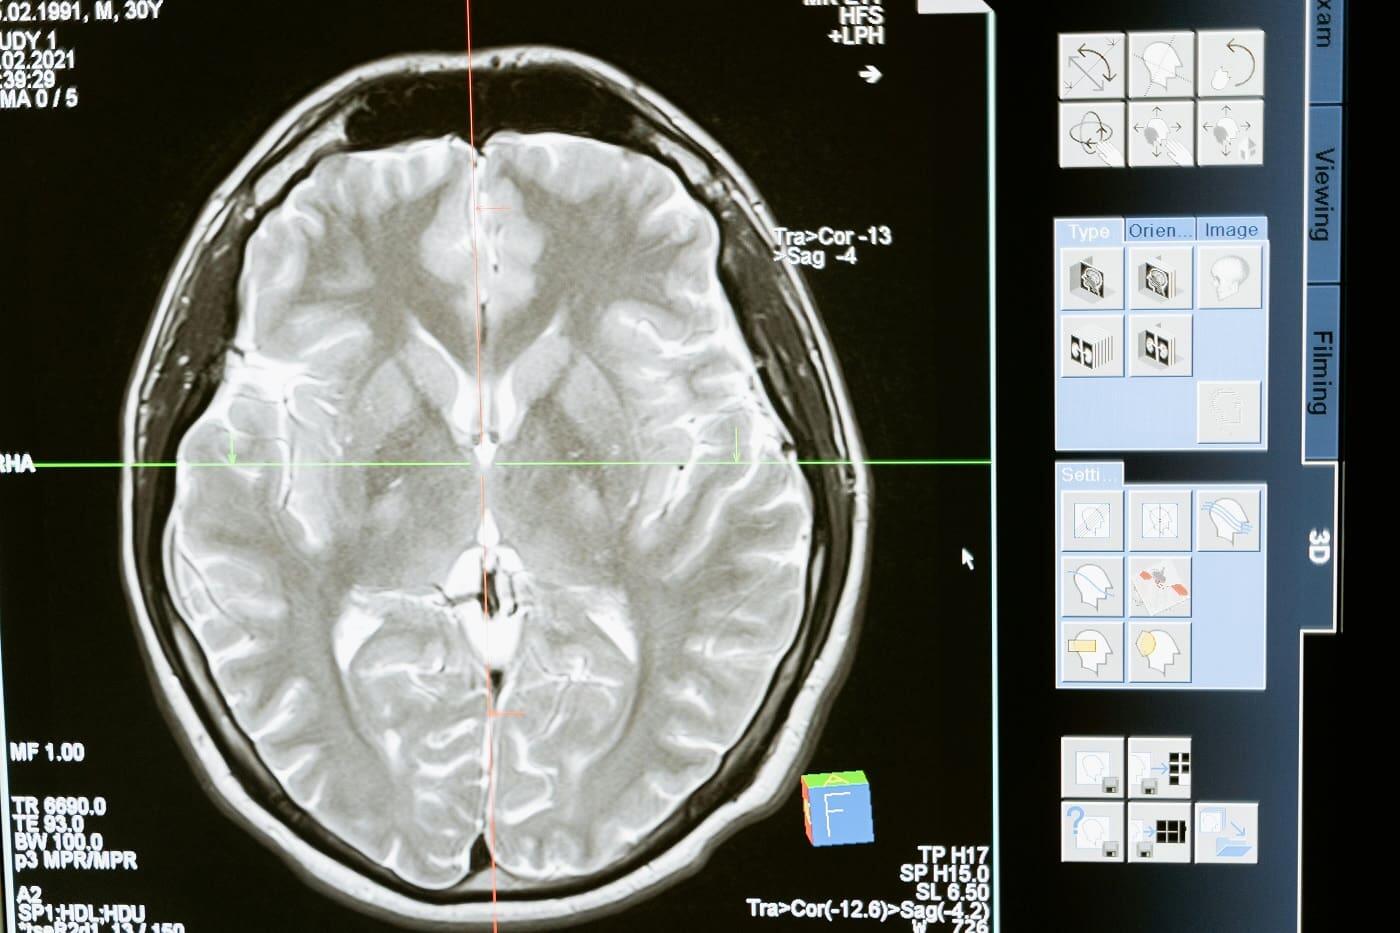

- Moždani udar je oštećenje dela moždanog tkiva koje nastaje usled začepljenja krvnog suda u mozgu ugruškom to je ishemijski moždani udar, ili zbog pucanja krvnog suda i izlivom krvi u moždano tkivo ili moždane opne to je hemoragijski moždani udar. Kod ¾ pacijenata koji su doživeli moždani udar nalazimo hiperternziju kao ključni faktor rizika. Zato je važno na vreme otkriti i lečiti povišeni krvni pritisak. Pored toga, od velikog je značaja sniženje povišenog holesterola, prekomerne telesne mase, kao i prestanak pušenja i zloupotrebe alkohola – upozorava dr Danijela Stamnišić Srdić specijalista kliničke farmakologije i direktor Rx portfolija za Zapadni Balkan, Hemofarm– STADA.

Moždani udar, promene vremena (Pexels)